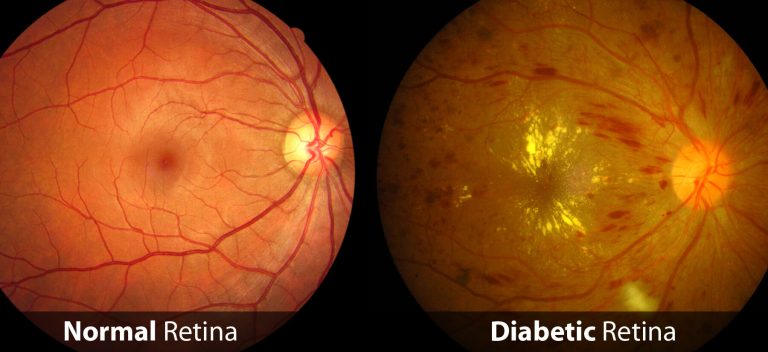

In a normal condition, our eyes is similar to how your old camera functions. There’s lense in front eye and a layer of film at the back. The optic nerve called retina resembles a film in a camera.

The centre of eyesight located on the retina called macular

Macular hole is a disease that is caused by a hole at the centre of the eye.

Refer below picture to understand more :